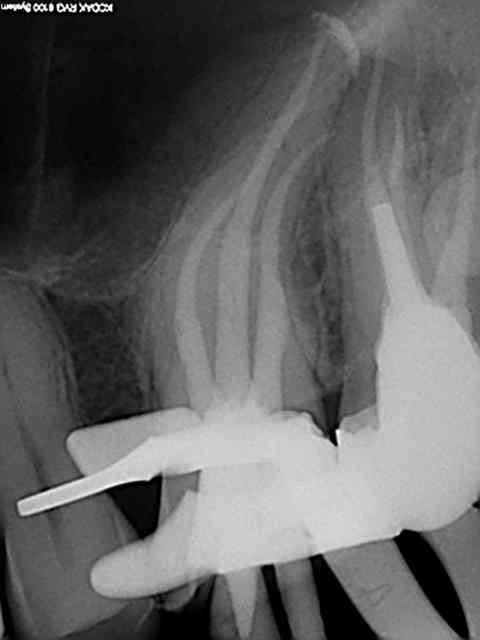

60 mn environ pour ces 2 là, le canal mv2 augmente le temps d'exéctution de 15 à 30 mn surtout si l'entrée est proche du mv1. Il n'y a pas photo entre la préparation canalaire du r25 VS f2 protaper.

Comme les protapers, ca remplace le s2,f1 f2 et ça casse pas. Recherche des canaux avec le sx sur entran , ouverture largo n°3, re sx pour progresser apicalement, s1 sur endomaster pour lt, r25 sur wd silver et terminé (si le s1 ne va pas direct à l'apex un coup de r25 peut s'avérer nécessaire pour les canaux longs et courbes comme sur la 16 ci-dessus ou la lt était à 25 mm)